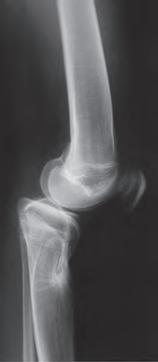

Rycina 17.81.

A, B – Genu recurvatum u pacjenta po złamaniu okolicy proksymalnej części chrząstki nasadowej piszczeli.

Rycina 17.82.

Uszkodzenie tętnicy podkolanowej wskutek złuszczenia nasady bliższej kości piszczelowej (S-H 1). Zagrożenie rozwojem zespołu przedziałów powięziowych jest poważne.

Rozpoznanie

Objawy złamania to silny ból uniemożliwiający stanie i chodzenie, zniekształcenie obrysów stawu kolanowego przez krwiak i różnego stopnia przemieszczenie nasady kości piszczelowej. Należy dokładnie zbadać stan ukrwienia i unaczynienia kończyny pod kątem objawów uszkodzenia tętnicy podkolanowej i nerwu strzałkowego. Trzeba ocenić bolesność uciskową oraz napięcie w przedziałach powięziowych podudzia: przednim, bocznym, tylnym powierzchownym i tylnym głębokim. U pacjentów z podejrzeniem wzmożonego ciśnienia wewnątrzprzedziałowego należy wielokrotnie powtarzać badanie ukrwienia i unerwienia kończyny, a w razie zaistnienia wskazań wykonać bezpośredni pomiar ciśnienia w przedziałach. Powinno się zawsze podejrzewać możliwość uszkodzeń więzadłowych współistniejących ze złamaniem. Badania obrazowe to RTG w pozycji AP, bocznej i skośnej. Wykonanie badania TK może być konieczne w celu pełnej oceny rozległości

złamania. W przypadku podejrzenia uszkodzenia tętnicy podkolanowej należy wykonać angio-TK lub arteriografię.